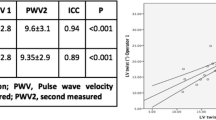

There are several different tools to non-invasively assess PWV, including tonometric and oscillometric methods as well as CMR-based techniques [49, 50]. Many studies focus on comparing different approaches to PWV assessment and try to determine the simplest and most reliable methods that could be helpful in everyday practice [49, 51, 52]. Recent research, dedicated to comparing different CMR-based techniques of aortic stiffness evaluation in hemodialysis patients, demonstrated excellent inter- and intra-observer variability of ascending and descending AD as well as aortic PWV measurements. The study did not show any significant correlations between inter-study changes in markers of cardiac loading and hydration status as well as in aortic stiffness measures; provided that patients are scanned under the standardized conditions. CMR-derived measures of aortic stiffness seem to be reproducible and unaffected by the changes in fluid status. All three parameters of aortic stiffness were associated in this study with indexed LV mass on univariate analysis [53].